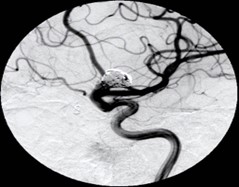

「科普」脑动脉瘤是如何形成的?

脑部动脉瘤的形成是一个复杂的过程,涉及多种因素的相互作用,包括遗传因素、环境因素、血管壁先天性缺陷、动脉粥样硬化、感染、创伤等,出现头痛、恶心、呕吐等疑似动脉瘤破裂的症状时,应立即就医检查并接受相应治疗。

脑部动脉瘤是很严重的事情,因为脑部动脉瘤俗称颅内定时炸弹。这种动脉瘤一旦破裂,则会引起灾难性的后果。经过统计学表明,一次破裂之后,有1/3的人会当场死亡;如果再破裂第二次,剩余的1/3的人也会死亡。在临床当中,破裂三次乃至于三次以上的患者,基本上没有存活下来的概率。哪怕是经过积极治疗存活之后,更多的是植物生存状态,根本没有生活自理能力。所以对于脑部动脉瘤,一定要及时进行相应的处理。术后也面临非常多的风险,比如脑肿胀、脑血管痉挛,甚至引起梗死等各方面的病情变化。所以脑部动脉瘤是非常严重的,一定要到大型医院进行就诊,并且及早查明原因,及早进行手术治疗,单纯的内科药物是没有办法治愈的。